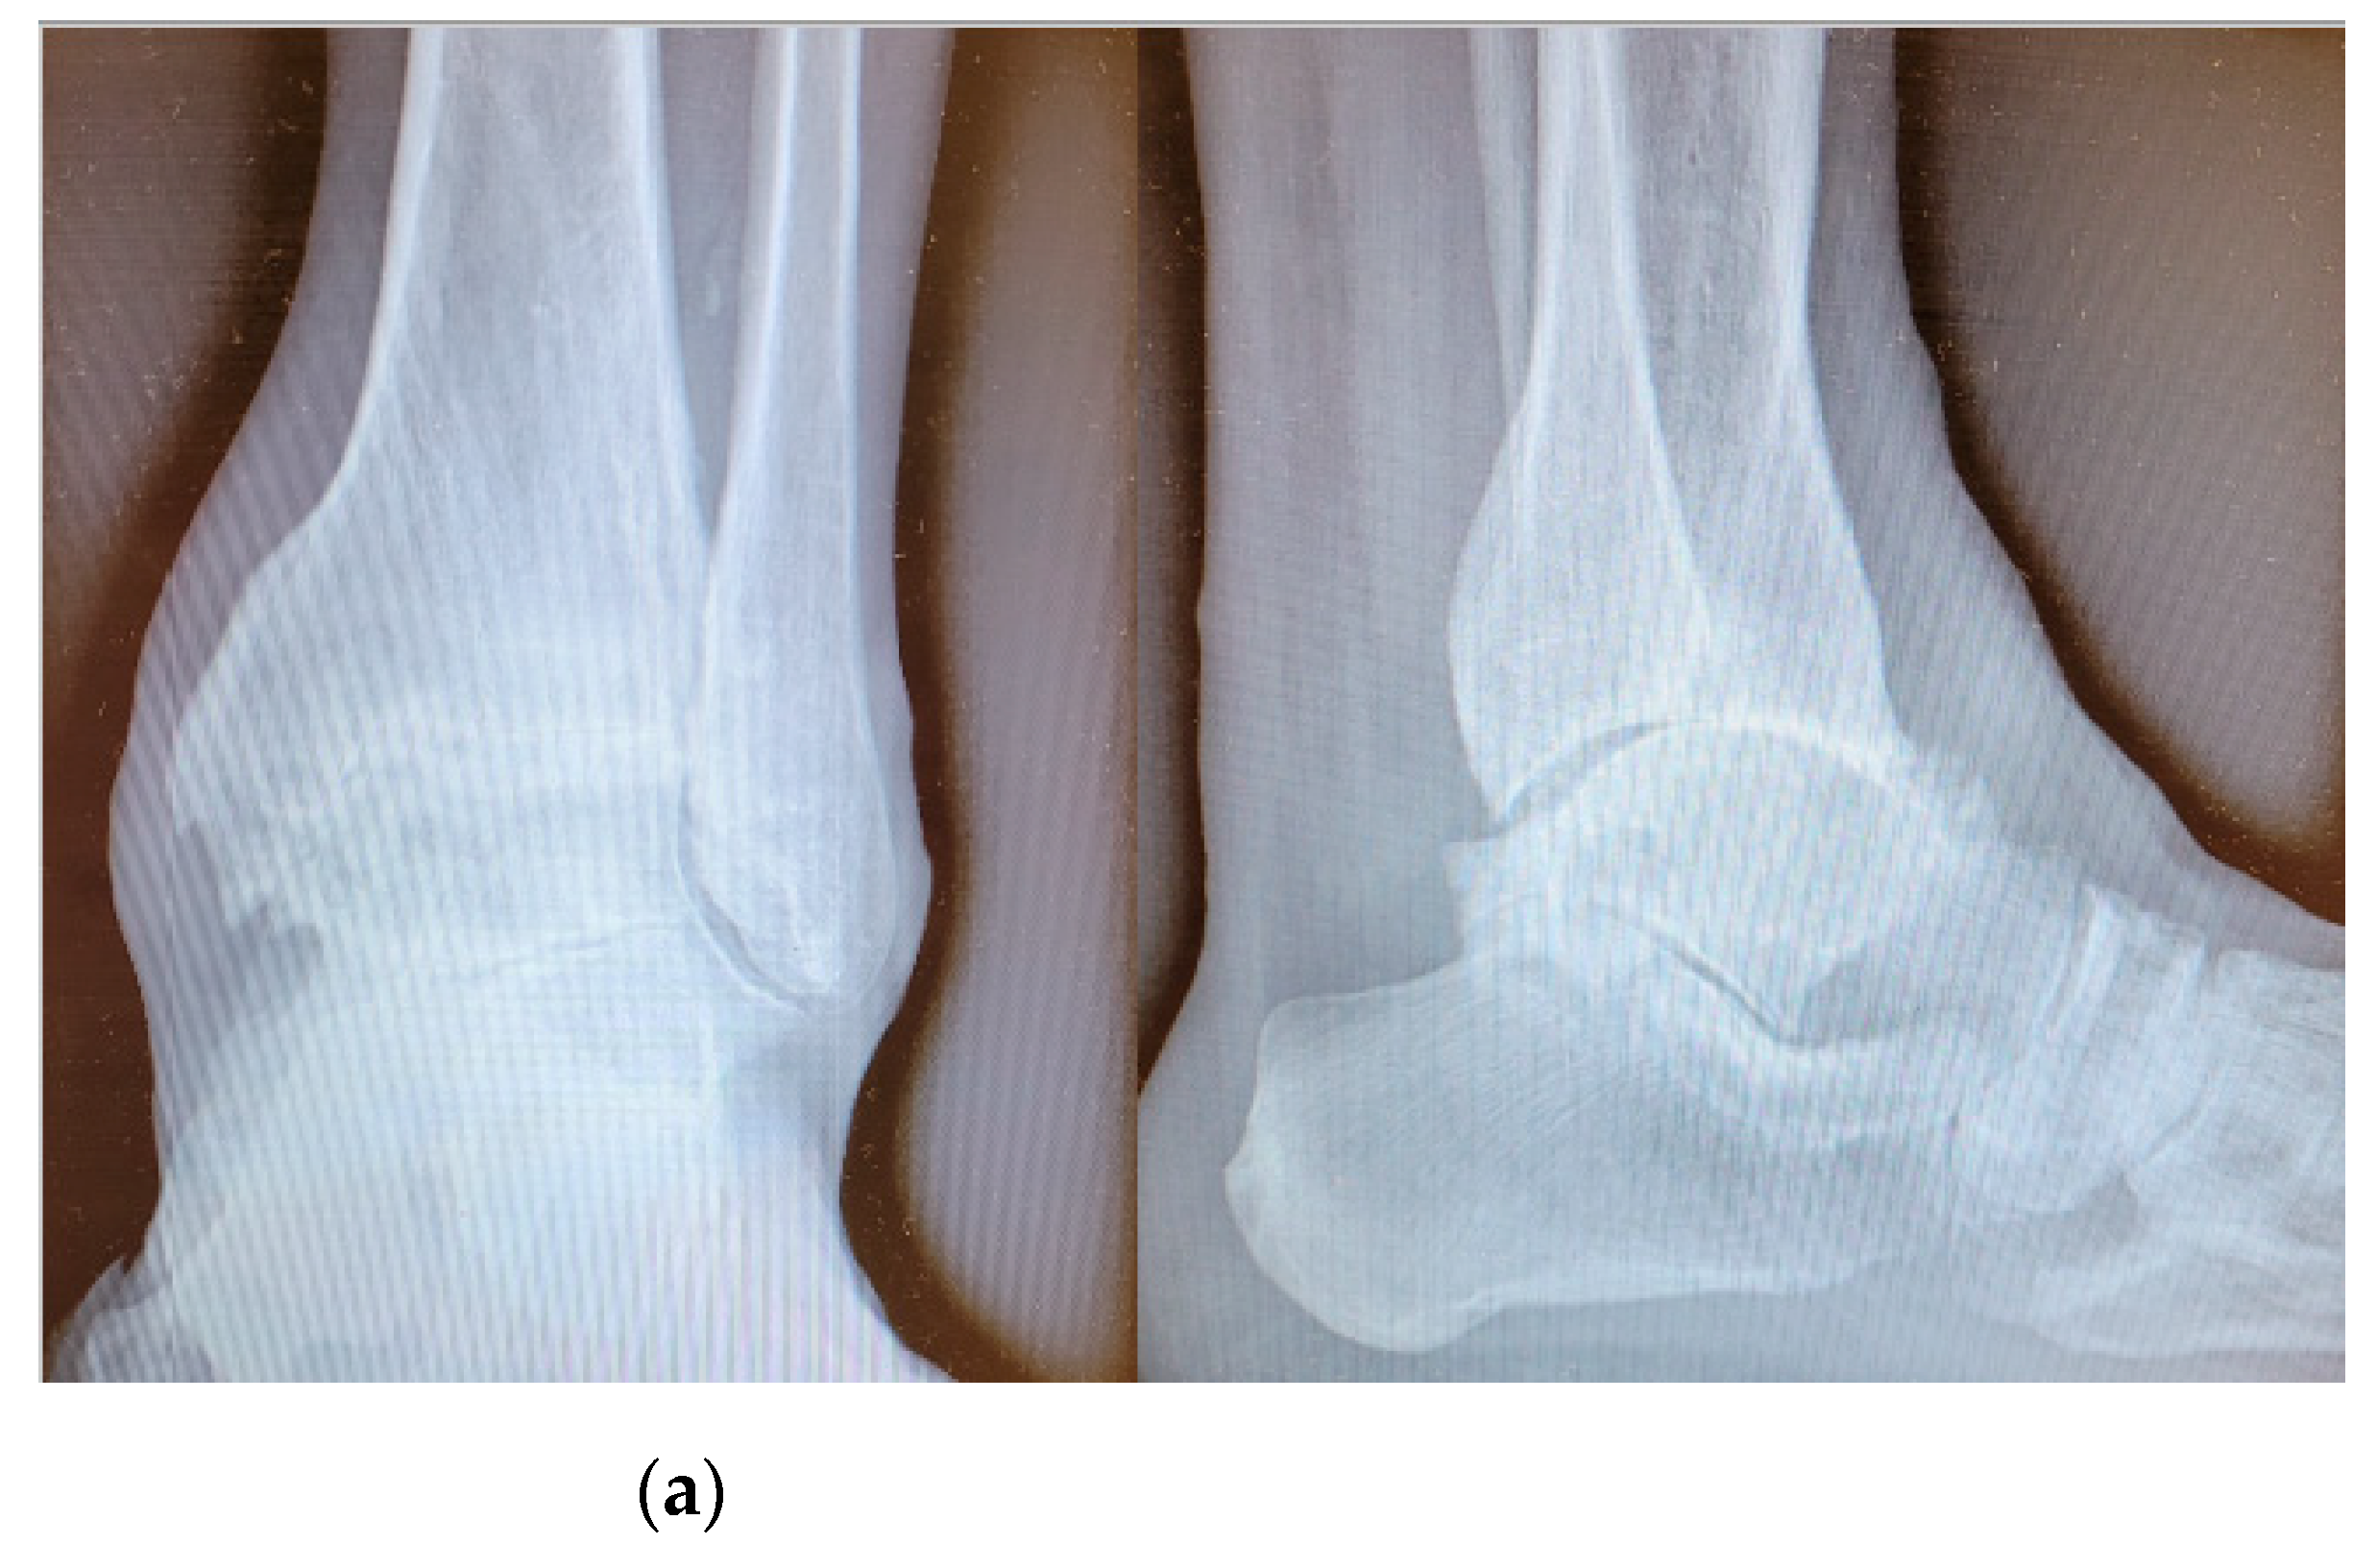

Figure 1.

Pre-operative radiographic image in anteroposterior and lateral view (on the left and on the right, respectively) of an arthritic ankle joint, with a slight articular varus deformity (a) and post-operative radiographic results (b).